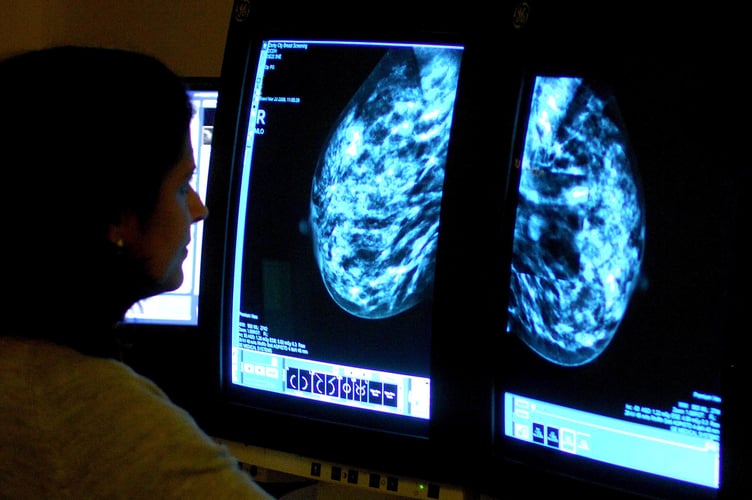

The rise follows NHS England’s first-ever breast screening awareness campaign to encourage more women to attend potentially life-saving mammographies in order to help detect cancers earlier.

NHS England figures show 135,709 women aged between 53 and 71 in Hampshire underwent a breast screening in the three years to March – up from 127,910 in the three years to March 2023.

It means 77.3% of eligible women in the area were screened over the last three years – up from 73.9% between 2020-21 and 2022-23.